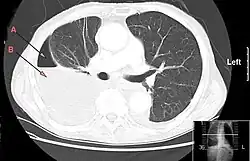

Als Empyem bezeichnet man seit der Antike eine Ansammlung von Eiter in einer vorgeformten (meist natürlichen) Körperhöhle oder in einem Hohlorgan. Beispiele für Empyeme sind das Gallenblasenempyem, das Kieferhöhlen-Empyem, das subdurale Empyem (im Subduralraum[2]), Lungen- und Pleuraempyem (Brust-Rippenfell-Zwischenraum)[3] sowie verschiedene Gelenk-Empyeme (Pyarthros). Eiteransammlungen ohne vorgeformte Körperhöhle nennt man im Gegensatz dazu Abszess,[4][5] doch erfordert die Unterscheidung mitunter bildgebende Verfahren.[6] Eine sich diffus in den Weichteilen ausbreitende eitrige Infektion nennt man Phlegmone.[5] Ein Empyem, das sich als Abszess ausbreitet und gegebenenfalls die äußere Körperwand, z. B. die Thoraxwand, durchbricht, nennt man Empyema necessitatis.[7]

Neben der Anamnese, der körperlichen Untersuchung und der Labordiagnostik (CRP und Leukozyten) sind zur Lokalisation Untersuchungen wie Computertomografie, Magnetresonanztomografie oder Sonografie (Ultraschall) hilfreich.